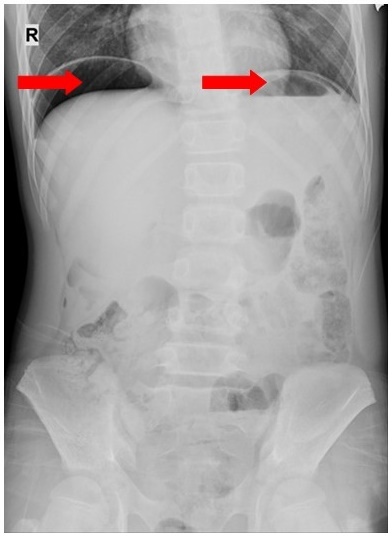

Hình ảnh liềm hơi dưới hoành hai bên trên phim chụp X-quang ổ bụng của bệnh nhân D. Ảnh: BVCC.

Qua thăm khám và chụp X-quang bụng, các bác sĩ nhận thấy D. bị thủng tạng rỗng, chỉ định phẫu thuật nội soi cấp cứu.